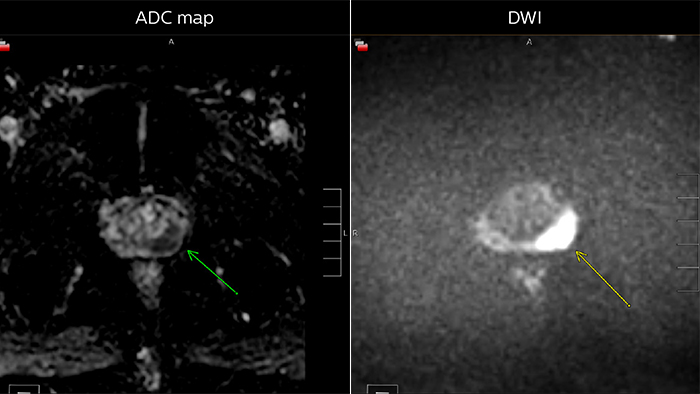

“We also look at diffusion-weighted images and the ADC map. Prostate neoplasms generally have diffusion restriction, so they are bright on diffusion-weighted imaging and dark on an ADC map, which is one of the most important characteristics of neoplasms.”

“The third characteristic we look at, flow, is somewhat less specific but may be quite important in deciding whether a lesion is significant or insignificant. Prostate neoplasms often have a hypervascular tumor flow pattern, meaning that there is rapid inflow of blood into the lesion and then rapid outflow due to a disrupted capillary bed. This can be graphed on multi-parametric images, allowing us to define regions of interest and look at the actual flow within these regions.”

Multiparametric MRI of a classic peripheral zone lesion Dr. Steiner describes this case: “For lesions in the peripheral zone of the prostate, the DWI (diffusion weighted imaging) and ADC map are most helpful for diagnosis. In this case, the DWI shows a very bright signal, which indicates diffusion restriction. The arcuate area with significant signal drop out (arrow) on the ADC map is recognized as highly suspect for tumor. On the axial T2-weighted image the capsule contour looks a little irregular (arrow), which we interpret as capsular disruption, and I usually give a measurement: this lesion shows larger than 1.5 cm capsular disruption. I don’t see any signs of lymphadenopathy, but interpret this lesion as PI-RADS 5. The hypervascular flow pattern in the bottom images adds to the diagnostic confidence.”